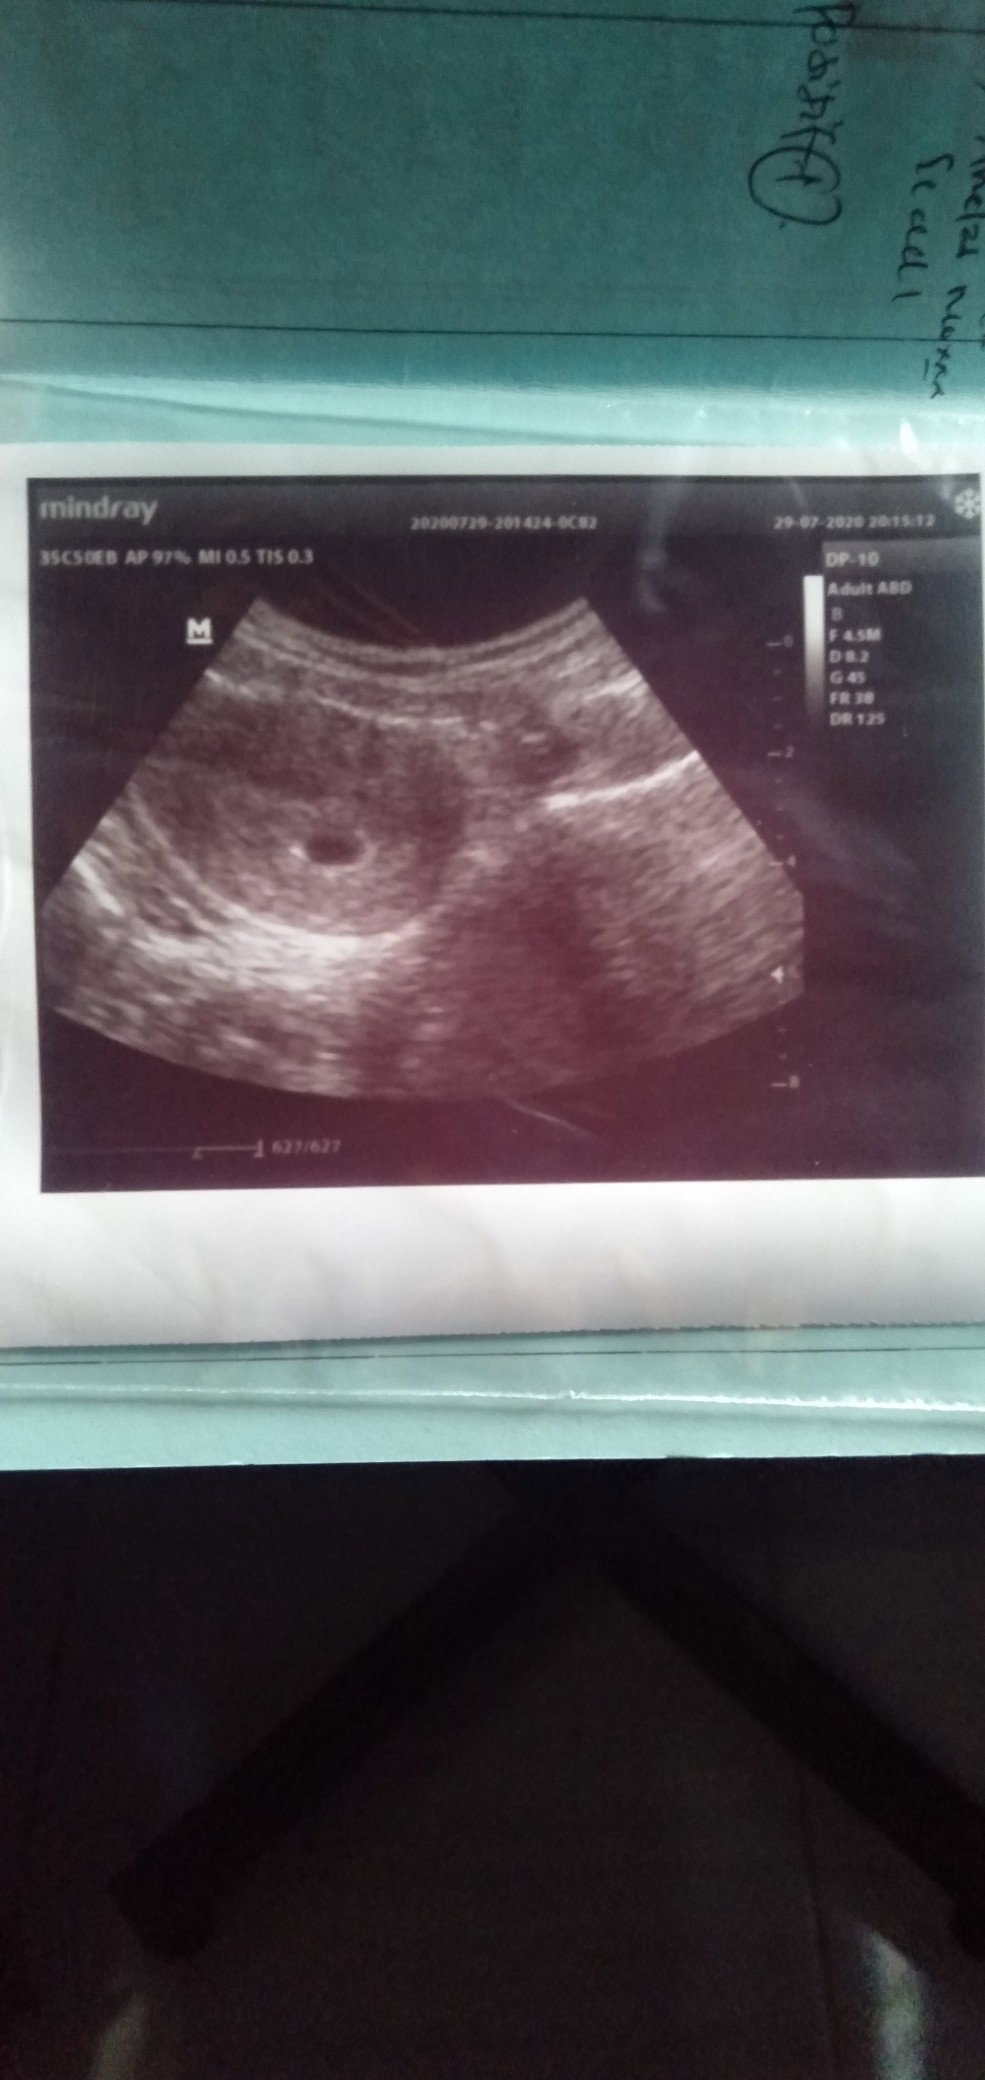

USG WEEK 6 DI KATAKAN KEMBAR

Ada yg pernah gini gak bun waktu priksa usg di katakan kembar tapi di lihat nya dari mana yah ?